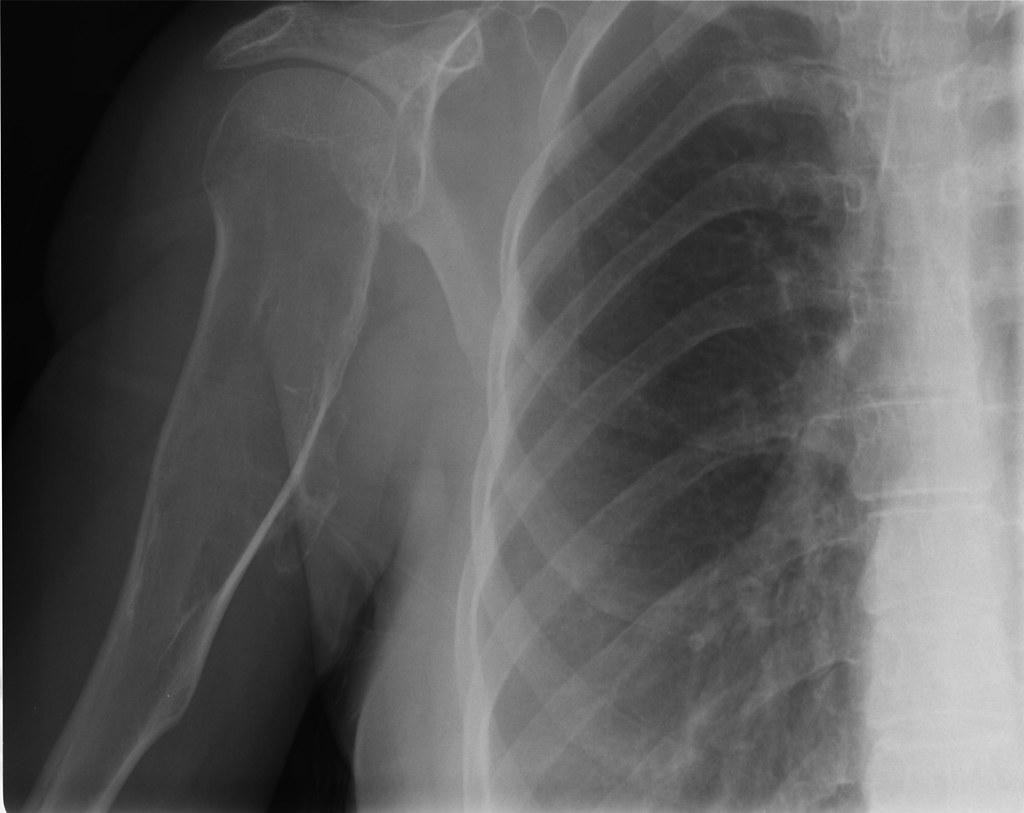

from www.tamingthesru.com

Xray Vision Shoulders and Elbows — Taming the SRU